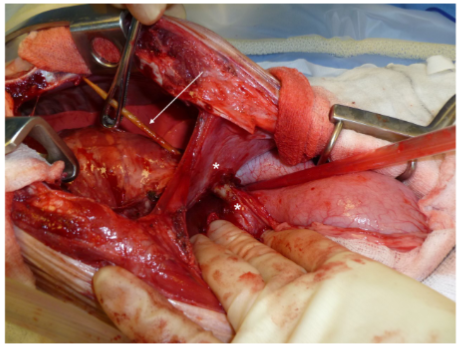

오뎅 꼬치의 나무를 먹고 흉강으로 이동한 11케이스

특히 나무가 일종의 빨대가 되어 모세관 현상을 통해 똥물을 복강으로 흘려보내니 복막염 또한 어마어마한게 보통...